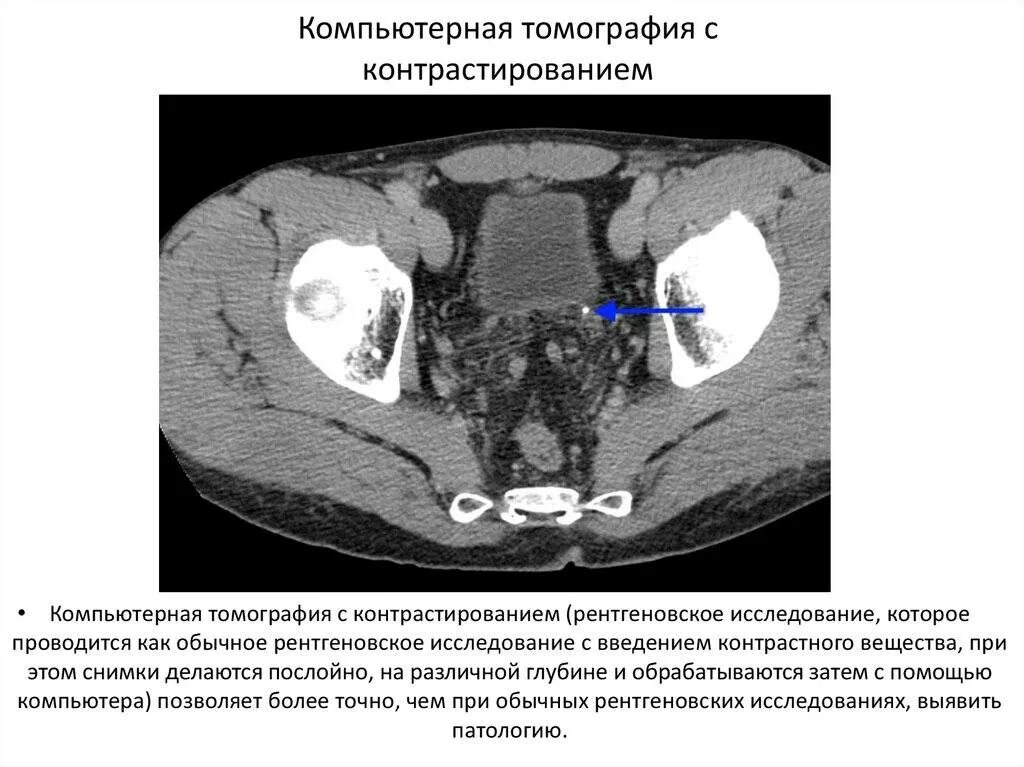

Плохо после контраста кт